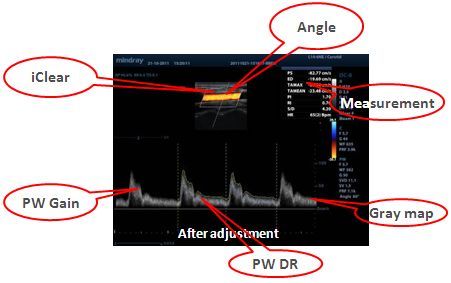

iTouchTM

–Я–Њ–Ј–≤–Њ–ї—П–µ—В –≤—Л–њ–Њ–ї–љ—П—В—М –Љ–≥–љ–Њ–≤–µ–љ–љ—Г—О –∞–≤—В–Њ–Љ–∞—В–Є—З–µ—Б–Ї—Г—О –Њ–њ—В–Є–Љ–Є–Ј–∞—Ж–Є—О –Є–Ј–Њ–±—А–∞–ґ–µ–љ–Є—П –≤ —А–µ–ґ–Є–Љ–∞—Е –Т, –њ—А–Є —Ж–≤–µ—В–Њ–≤–Њ–Љ –Є –Є–Љ–њ—Г–ї—М—Б–љ–Њ-–≤–Њ–ї–љ–Њ–≤–Њ–Љ –і–Њ–њ–њ–ї–µ—А–µ (PW) –љ–∞–ґ–∞—В–Є–µ–Љ –Њ–і–љ–Њ–є –Ї–ї–∞–≤–Є—И–Є.